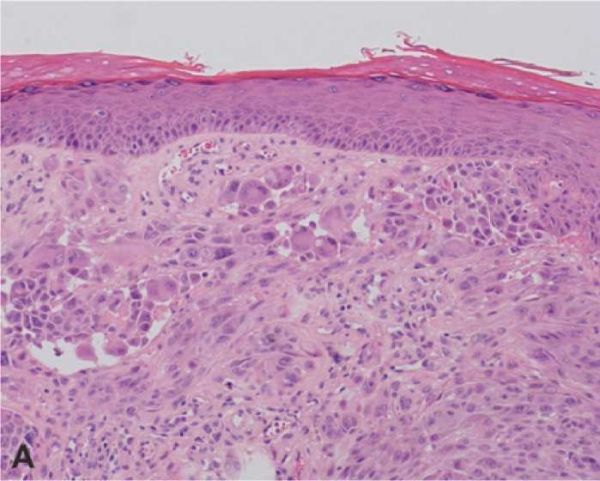

הקושי האבחנתי המתמשך באבחון שומות שפיץ נובע מכך שהן מורכבות מתאים מלנוציטריים בעלי מורפולוגיה דומה לתאי מלנומה: התאים גדולים, אפיתליואידיים וכישוריים, בתערובת משתנה. ניכרים בתאים גרעינים וסיקולריים, פליאומורפיים, עם גרעינונים בולטים וציטופלזמה איאוזינופילית אחידה. בנוסף, בכמחצית מהשומות ניכרת פעילות מיטוטית במרכיב הדרמלי, ממצא שהוא נדיר בשומות רגילות. עם זאת, פעילות מיטוטית בעומק הנגע ומיטוזות אטיפיות, אינן אופייניות. בדומה לשומות רגילות, שומת שפיץ מתפתחת ככל הנראה באפידרמיס, לאחר מכן היא מערבת הן את האפידרמיס והן את הדרמיס, ובשלבי התפתחות מאוחרים יותר כולה תוך-דרמלית.

בספקטרום זה מצויים נגעים קשים לאבחון, שבאבחונם לא קיימת הסכמה גם בין המומחים הוותיקים בעולם בתחום הדרמטופתולוגיה. נגעים אלה מכונים שומות שפיץ אטיפיות (Atypical Spitz nevus or tumor). ההיארעות של נגעים אלה לא ידועה בוודאות, אך יש הגורסים שכ-6 עד 8 אחוזים משומות שפיץ הן שומות שפיץ אטיפיות. לנגעים אלו, המופיעים בכל הגילים, תכונות מורפולוגיות המזכירות שומת שפיץ, אך נצפים בהם ממצאים מדאיגים, כגון צלולריות בולטת, מעורבות עמוקה של הדרמיס ואף של שומן תת-העור, היעדר הבשלה, התכייבות של הנגע ופעילות מיטוטית ערה בכל חלקי הנגע. עם זאת, הממצאים אינם מספיקים לקביעת אבחנה של מלנומה, והפתולוג נאלץ לאבחן שומת שפיץ "אטיפית" שהתנהגותה הביולוגית אינה ברורה (תמונה מספר 1).